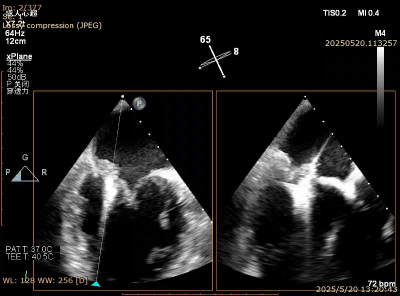

图5. Barlow样改变,A3,P2, P3脱垂,后叶甩动厉害

图6. XTR 一枚夹合 2区,后叶难以夹多

图7. 倒挂金钩,夹合更多瓣叶